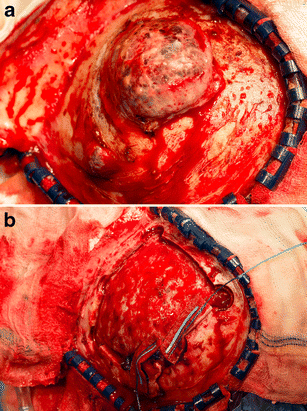

a The tumor was fixated to the skull, but not to the skin and subcutaneous tissue, which could easily be separated from the tumor surface. b No dural defects were detected after removal of the bone flap